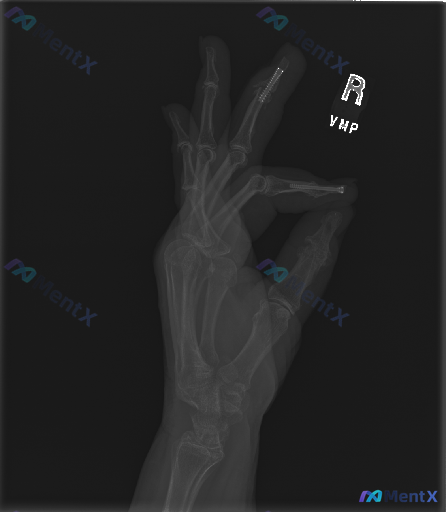

整理到一份右手X光正位片的影像资料,大家一起讨论下: 影像观察到的主要信息: - 右手各掌骨、指骨及腕骨形态大致正常,骨皮质连续性未见明显中断,骨小梁纹理清晰 - 最突出的表现是:右手示指(第2指)和中指(第3指)的近节指骨内,分别可见一枚纵向植入的金属螺钉,钉道走行与骨干长轴平行 - 螺钉周围骨质...